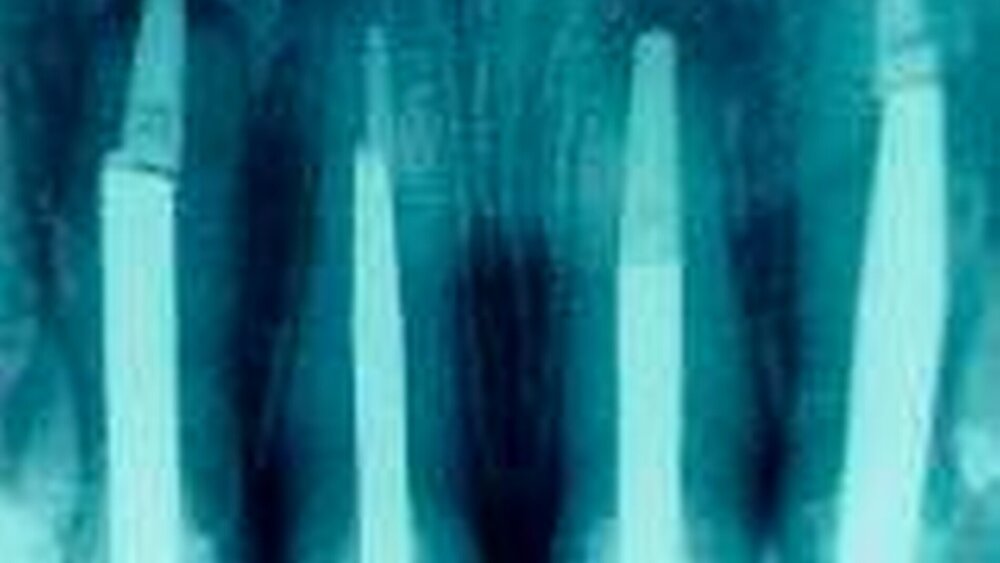

Das Orthopantomogramm ergab über den klinischen Befund hinaus keine Besonderheiten. Ein Vergleich der Einzel-Röntgenbilder der wurzelspitzenresizierten Zähne direkt nach dem operativen Eingriff und dem aktuellen Stand machte die fast vollständige Ossifikation der Resektionshöhlen sichtbar.

Das Kontroll-Röntgenbild 18 Monate nach Eingliederung zeigt keine apikalen Veränderungen (Abbildung 20).